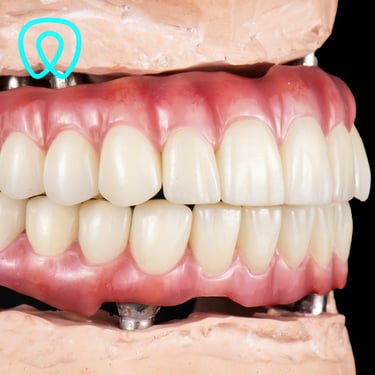

Contamos con todas las especialidades dentales: ortodoncia, implantes, cirugía, endodoncia, periodoncia, odontopediatría, odontología cosmética, prótesis dental.

Servicios Dentales

Atención integral en odontología para todas las edades y especialidades con enfoque en la prevención.